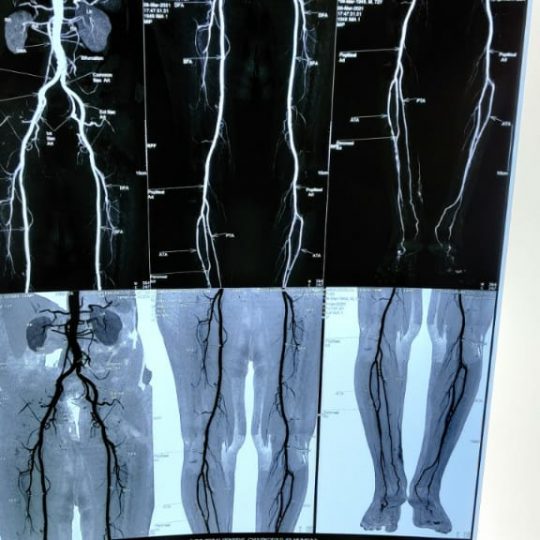

Patient’s Successfully Treated with Diabetic Foot Problems